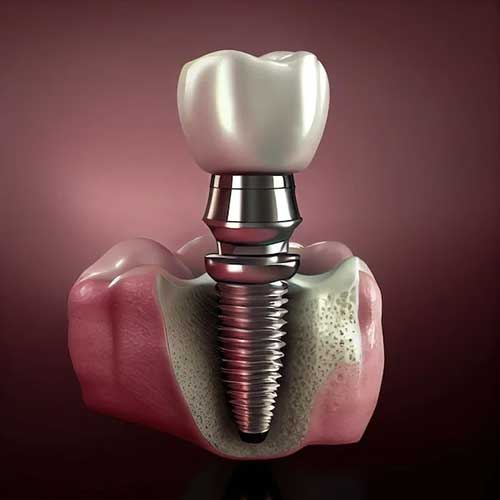

AUD 300

Dental Implants